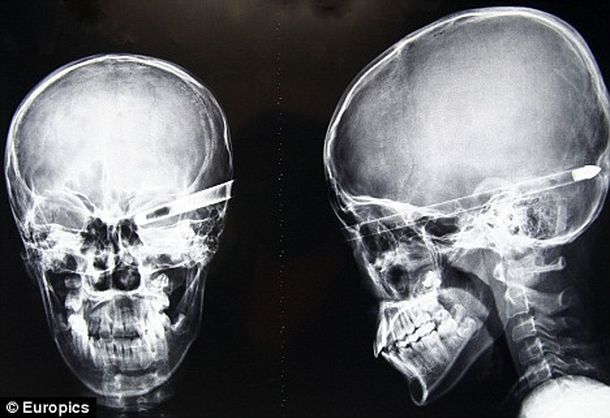

Un chico de nacionalidad china sobrevivió “milagrosamente” después de que su compañero le disparara por accidente una flecha en el ojo. La operación para remover la flecha llevó cuatro horas, pero el chico se salvó porque el cerebro no sufrió daños.

Liu Cheong, un estudiante de 11 años de la ciudad china de Jiutai, sobrevivió después de que su compañero le disparara una flecha de 40 centímetros que le entró por el ojo y se detuvo recién al llegar al lado interno del cráneo, según publicó el sitio británico Daily Mail.

Mientras tnato, los médicos que atendieron el caso de Liu declararon que fue un “milagro” que hubiera sobrevivido. “Si la flecha hubiera sido disparada con un poco más de fuerza”, declaró uno de los médicos, “le hubiera salido por el otro lado del cráneo”.

Pero la flecha, que atravesó los órganos internos de la cabeza de Liu, no llegó a tocar el cerebro, lo que dio lugar para el milagro de Liu, según pudieron comprobar los médicos, que tuvieron que cortar parte de la flecha para poder hacerle una tomografía.

Liu todavía no se encuentra del todo fuera de peligro, aún después de cuatro horas de operación para remver la flecha de su cabeza. Todavía quedan por delante posibles infecciones y próximas operaciones que tendrá que enfrentar.